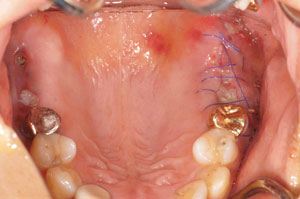

@@R.S‚³‚ñ@56Î —«  ‘åŠw‹³Žö @Žèp“ú@‚Q‚O‚O‚W”N ‚QŒŽ ‚X“úi“yj@㉺Š{  ƒm[ƒxƒ‹ƒKƒCƒhŽg—p@Ö¬“à’ÁÖ@•¹—p@@@

@@@@@ãŠ{  All on ‚U@‘¦Žž‰Ád@@

@@@@@@@@@@@@@ Rpl Tapered Rp  ‚P‚O mm(‚U–{)

@@@@@‰ºŠ{¶‰E@‘¦Žž‰Ád@ ‚R Unit Bridge@

@@@@@@@@@@@ @Rpl Tapered Rp  ‚P‚O mm(‚S–{)@@–ƒWƒ‹ƒRƒjƒAƒNƒ‰ƒEƒ“‚ÅÅI•â’Ô